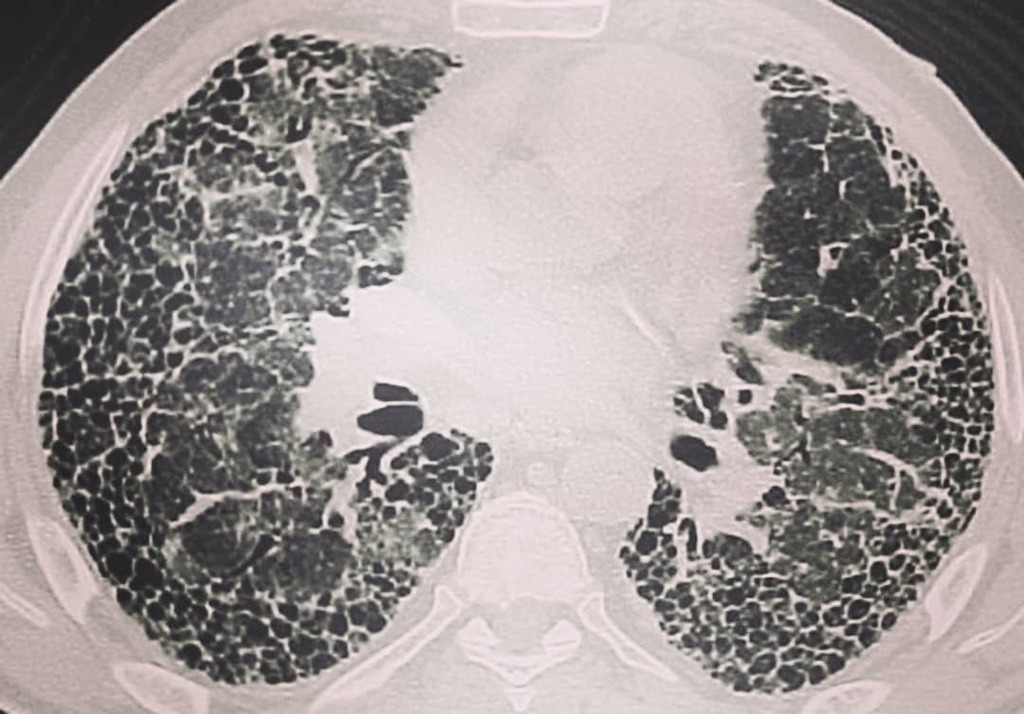

अगर आप थोड़ा सा भी चलते हैं तो आपका सांस...